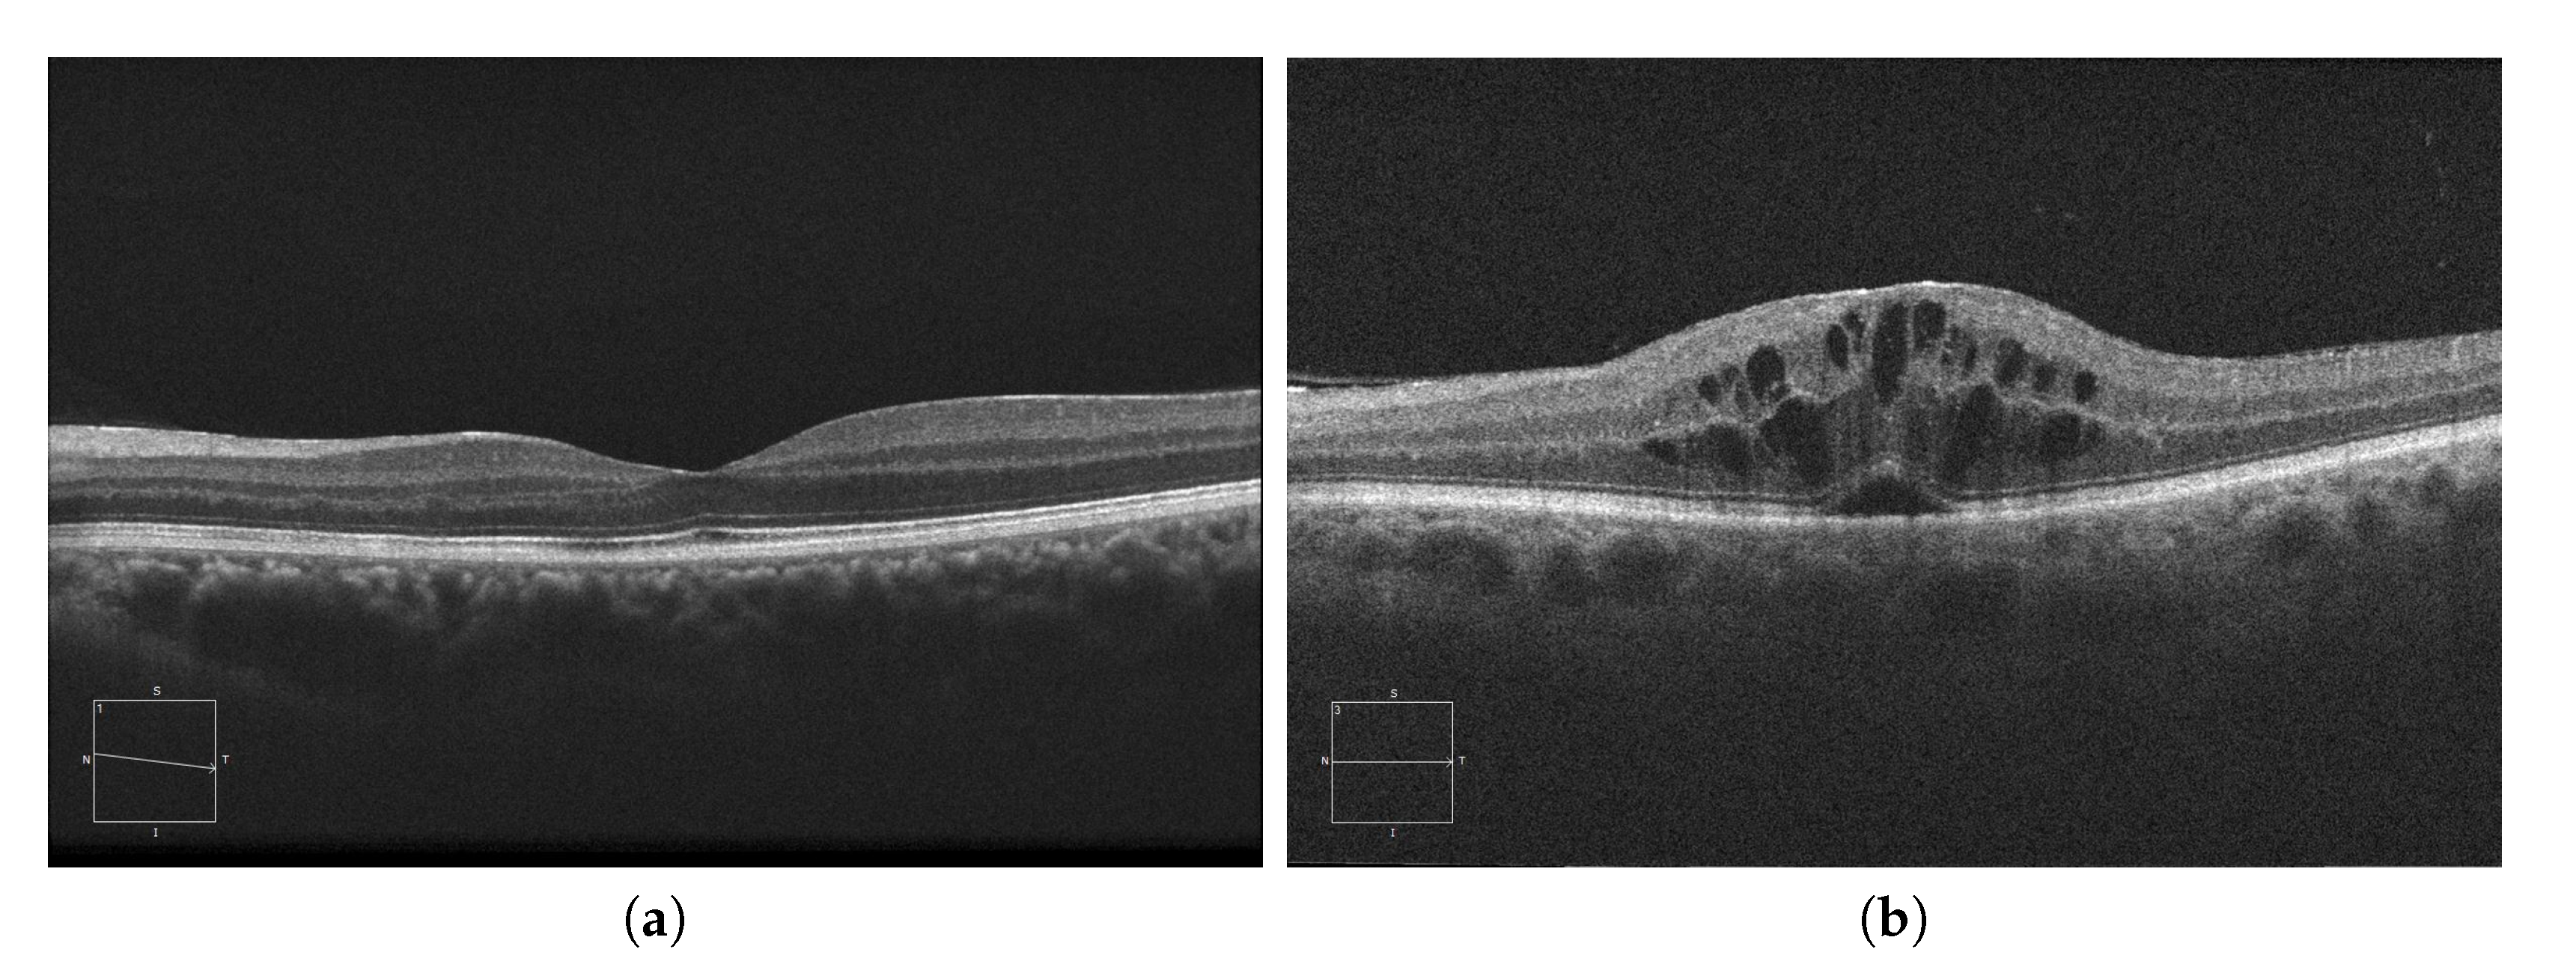

Currently, AMD is one of the most prevalent pathologies. It is especially relevant in developed countries, where it is among the main causes of blindness. The advance of this pathology can lead to abnormal vessel growth, resulting in fluid leakages from these malformed vessels. When this fluid begins to accumulate between the layers of the retina, the patient will begin to perceive a vision loss that may lead to blindness if left untreated. In Figure 1a, we can see an example of an OCT image of a healthy retina, whereas Figure 1b presents a retina with a perceptible accumulation of intraretinal fluid. For this reason, an early detection of these cystic bodies is critical, since it is not only an indicator of the severity of the pathology, but also helps clinicians to establish a more precise diagnosis and treatment [10].

Figure 1. Macular Optical Coherence Tomography (OCT) images. (a) OCT without the presence of cystoid regions. (b) OCT with the presence of cystoid regions.